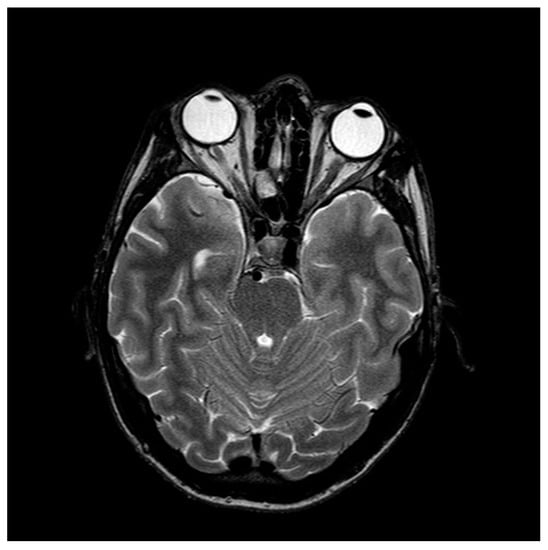

| 24 July–3 August 2020: hospitalization | At admission: BCVA RE, 0.5; LE, 0.5. At discharge: BCVA RE, 0.3; LE, 0.3 Ishihara color plate score: RE, 9/21; LE, 13/21; no relative afferent pupillary defect; central scotomas in both eyes Hyperemic and swollen optic discs, tortuous and distended vessels Diagnostic tests: full blood panel, serology, head and cervical spine MRI, genetic testing, ENT examination, neurological, electrophysiology Discontinued ciprofloxacin and linezolid, started on supplemental therapy with biotin; Vitamins B1, B6, and B12; and idebenone |